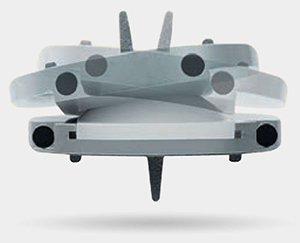

The prodisc L implant has been designed to maintain the physiological range of motion in the spine. The implant was developed using the clinically proven ball and socket concept used in joint replacement implants for over 40 years. The prodisc L implant is composed of three components – two cobalt chrome alloy (CoCrMo) endplates and an ultra-high molecular weight polyethylene (UHMWPE) inlay.

The prodisc implant is a ball and socket design with a fixed center of rotation. This patented design has been in clinical use since 1990 and utilized across the entire product platform. The fixed center of rotation allows physiological range of motion while providing stability to the spine and significantly reducing reoperations at the adjacent levels.

Secure Fixation

- Patented central keel and lateral spikes provide secure primary fixation

- Plasma-sprayed titanium surface on bone contacting surfaces promotes integration